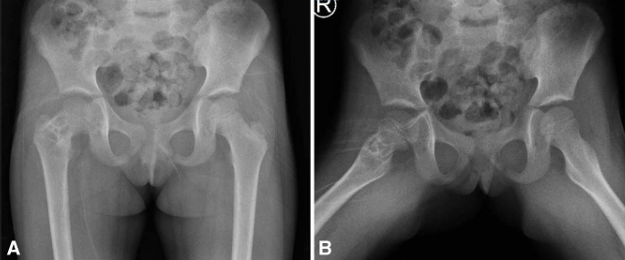

122.png

133.png